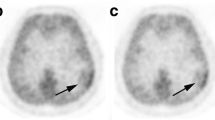

The MET-TAC patterns could be divided into four types for differential diagnosis of tumors (Fig. 1).

Schematic pattern of MET-TAC types. Type A shown by astrocytic tumors was a MET-TAC with a MET-SUV with a low or middle level in the initial phase, a rapid increase in the early phase, and a consistent or limited/slow increase in the late phase. The MET-TAC of the normal frontal cortex belonged to this type. Type O shown by tumors that included an oligodendroglial component was a MET-TAC with a MET-SUV with a low or middle level in the initial phase, a rapid increase in the early phase, and a limited/slow decrease in the late phase. Type L shown by PCNSL was a MET-TAC with a MET-SUV with a low level in the initial phase, a rapid increase in the early phase, and a continuous increase in the late phase. Type M/H shown by meningiomas and hemangioblastomas was a MET-TAC with a MET-SUV with a high level in the initial phase, a rapid decrease in the early phase, and a continuous decrease in the late phase. The MET-TACs of the confluence and internal jugular vein belonged to this type. MET-TAC time-activity curve of maximum tumor MET-standardized uptake value, MET-SUV maximum tumor MET-standardized uptake value

Type A, shown by astrocytic tumors, was a MET-TAC with a MET-SUV with a low or middle level in the initial phase, a rapid increase in the early phase, and a consistent or limited/slow increase in the late phase. The MET-SUV was markedly higher in the initial phase and had a tendency to increase more in early and late phases in GBM compared to AA and DA (Fig. 2a). MET-SUVs were significantly higher in early and late phases in GBM compared to AA, DA and the normal frontal cortex (*P < 0.05) (Fig. 2a). There was no significant difference in MET-SUVs between AA and DA (Fig. 2a). The MET-TAC of the normal frontal cortex belonged to this type, and the MET-SUVs of the normal frontal cortex were significantly lower than those of GBM, AA and DA (**P < 0.05) (Fig. 2a).

MET-TACs in brain tumors, the normal frontal cortex, confluence, and internal jugular vein. MET-SUVs were significantly higher in early and late phases (*P < 0.05) and showed a more marked increasing tendency in the early phase in GBM compared to AA, DA and normal frontal cortex (a). There was no significant difference in MET-SUVs between AA and DA (a). The MET-SUVs of the normal frontal cortex were significantly lower than those of GBM, AA and DA (**P < 0.05) (a). MET-SUVs were higher in the initial phase and showed a tendency to increase more in the early phase in AO compared to AOA, OD, and OA (b). There was no significant difference in MET-SUVs among AO, AOA, OD and OA (b). A tendency to decrease more was seen in the late phase in AOA, OD, and OA compared to AO (b). The MET-SUVs of OA were markedly lower than those of AOA and OD (b). MET-SUV with a low level in the initial phase, a rapid increase in the early phase, and a continuous increase in the late phase in PCNSL (c). MET-SUV with a high level in the initial phase, a rapid decrease in the early phase, and a continuous decrease in the late phase in meningiomas, hemagioblastomas, the confluence, and internal jugular vein (d). Error bars represent ± SEM, the 95% confidence interval. MET-TAC time-activity curve of maximum tumor MET-standardized uptake value, MET-SUV maximum tumor MET-standardized uptake value, DA diffuse astrocytoma, OD oligodendroglioma, OA oligoastrocytoma, AA anaplastic astrocytoma, AO anaplastic oligodendroglioma, AOA anaplastic oligoastrocytoma, GBM glioblastoma multiforme, PCNSL primary central nervous system lymphoma

Type O, shown by tumors that included an oligodendroglial component, was a MET-TAC with a MET-SUV with a low or middle level in the initial phase, a rapid increase in the early phase, and a limited/slow decrease in the late phase. The MET-SUV was higher in the initial phase and had a tendency to increase more in the early phase in AO compared to AOA, OD, and OA (Fig. 2b). There was no significant difference in MET-SUVs among AO, AOA, OD and OA (Fig. 2b). A tendency to decrease more was seen in the late phase in AOA, OD, and OA compared to AO (Fig. 2b). The MET-SUVs of OA were markedly lower than those of AOA and OD (Fig. 2b).

Type L, shown by PCNSL, was a MET-TAC with a MET-SUV with a low level in the initial phase, a rapid increase in the early phase, and a continuous increase in the late phase (Fig. 2c).

Type M/H, shown by meningiomas and hemagioblastomas, was a MET-TAC with a MET-SUV with a high level in the initial phase, a rapid decrease in the early phase, and a continuous decrease in the late phase (Fig. 2d). The MET-TACs of the confluence and internal jugular vein belonged to this type (Fig. 2d).